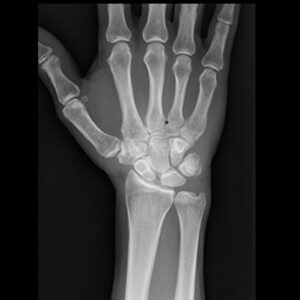

Reale Klinikbilder statt Demo-Grafiken.

Die spezialisierte Lernplattform für Projektionsradiographie. Im Mitgliederbereich steht eine stetig wachsende Fallsammlung mit realen Röntgenbildern zur Verfügung — systematisch aufgebaut, mit strukturierter Befundung, Befundcheck und klinisch relevanten Zusatzhinweisen.